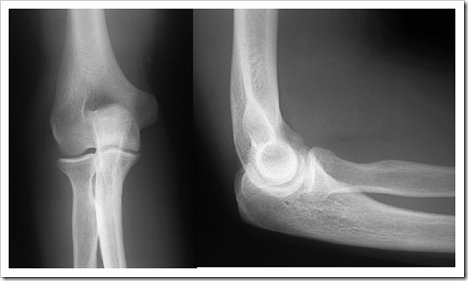

Gínglimo/ dobradiça: uma superfície côncava e outra convexa

Comporta-se como uma dobradiça de porta;

permite flexão e extensão Ex.: Articulação do cotovelo

Classificação quanto ao número de eixos: Mono-axial